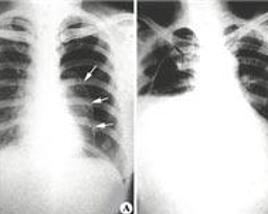

♥胸部阿米巴病

肠外阿米巴病中,肺和胸膜阿米巴病发生率仅次于肝脏,胸部阿米巴病右侧多发且大多继发于靠近膈肌的肝阿米巴脓肿,而肝阿米巴脓肿是肠阿米巴病的晚期并发症,胸部阿米巴病占阿米巴痢疾的1%~8%,占肝阿米巴病的15%~20%。